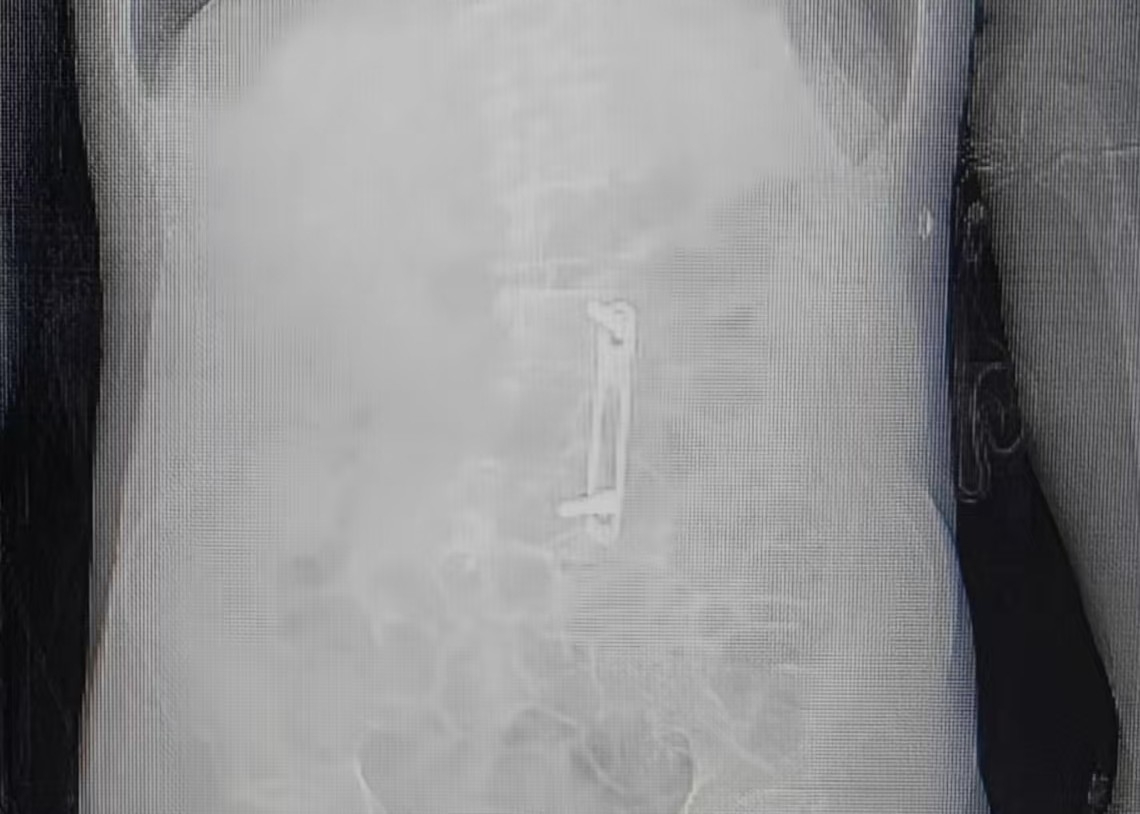

团队仔细研读患者腰椎CT影像后发现,腰2-3间隙结构仍保持完整,为单侧腰麻的实施提供了可能。

(患者腰椎内固定术后,腰2-3间隙结构仍保持完整)